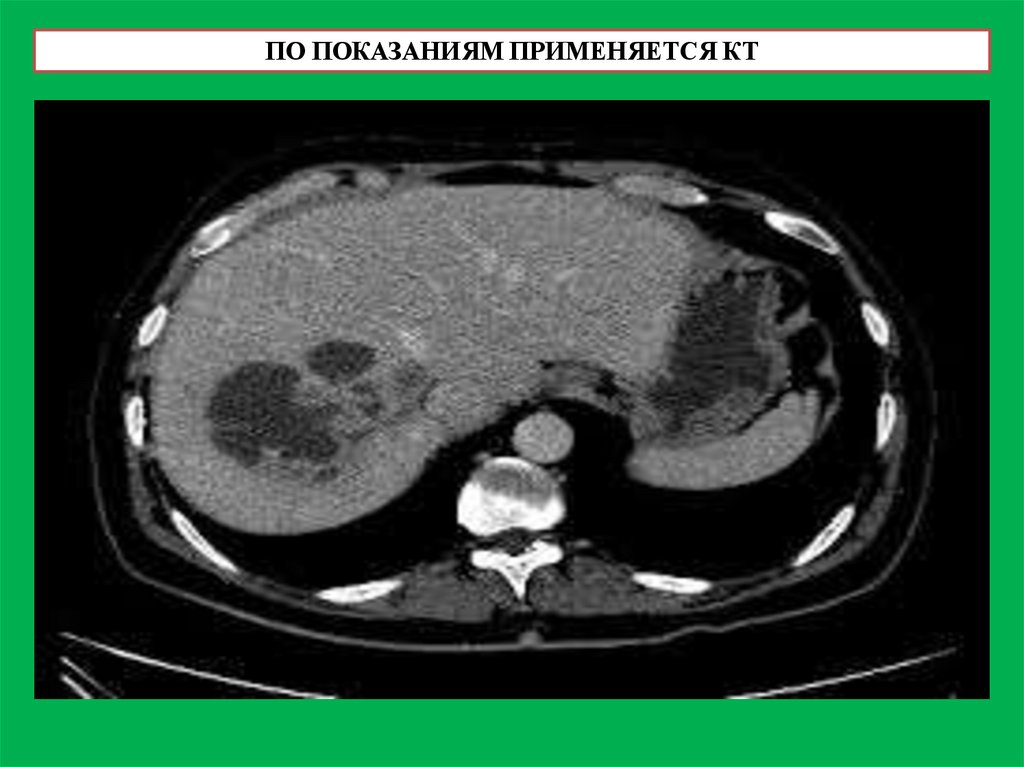

ПО ПОКАЗАНИЯМ ПРИМЕНЯЕТСЯ КТ

47.